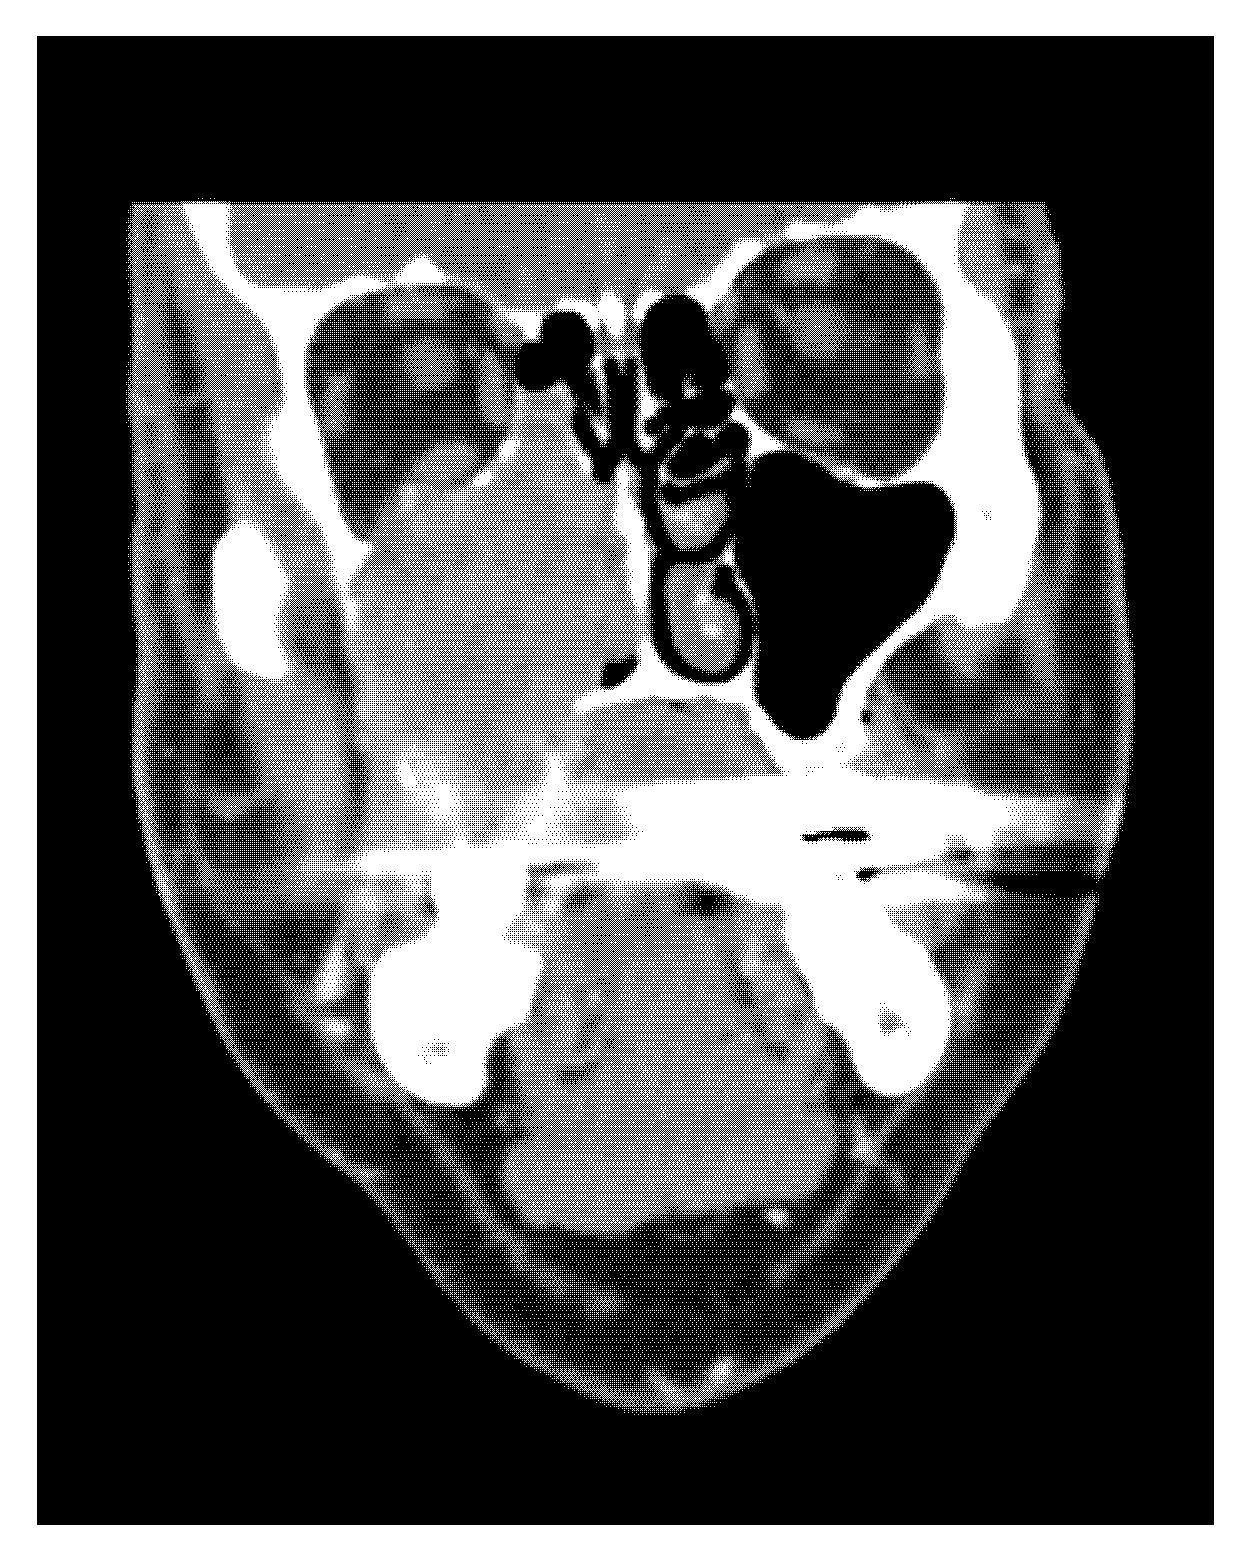

- CT, MRI scan (size, spread, and metastases of tumour mass), if necessary, PET scan, and USG.